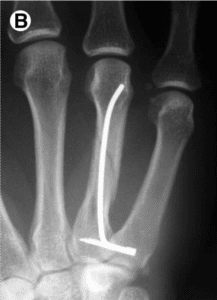

Fixation method for unstable bony mallet finger

A simple fixation method for unstable bony mallet finger A…